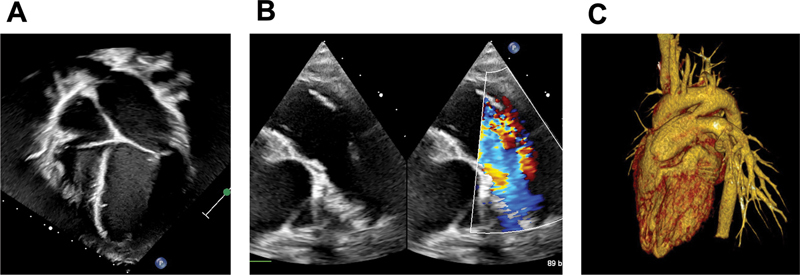

自从引入抗生素和手术或介入治疗策略以来,发生动脉导管未闭感染性动脉内膜炎(PDA-IE)的风险已大大降低。然而,PDA-IE 的诊断和充分、及时的治疗仍然具有挑战性。我们介绍了一例患有 PDA-IE 的 9 岁女孩的病例,说明了我们尽量减少儿科患者并发症的策略。

The risk of patent ductus arteriosus infective endarteritis (PDA-IE) has significantly reduced since the introduction of antibiotics and surgical or interventional treatment strategies. However, diagnosis and adequate, timely management of PDA-IE remains challenging. We present the case of a 9-year-old girl with PDA-IE, illustrating our strategy to minimize complications in pediatric patients.